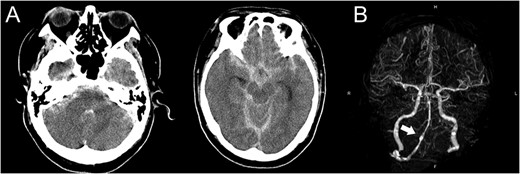

A 48-year-old man was admitted to our hospital because of loss of consciousness after a sudden nuchal pain. Brain computed tomography (CT) showed diffuse SAH (Fig. 1A). The following CT angiogram showed a fusiform aneurysm at the right vertebral artery with contralateral hypoplasia (Fig. 1B). The endovascular procedure was performed under general anesthesia. The patient received a loading dose of 200 mg of aspirin and 300 mg of clopidogrel via a nasogastric tube. A preoperative angiogram showed VAD with a blister at the pseudolumen (Fig. 2A). Initially, a stent (Enterprise, 4.5 mm × 37 mm; Codman, Raynham, MA, USA) was deployed from the basilar artery to the right vertebral artery. A second stent (Enterprise2, 4.0 mm × 30 mm) then overlapped the first stent, covering the pseudolumen (Fig. 2B). Coiling was performed from a microcatheter (Excelsior SL-10/45; Boston Scientific, Fremont, CA, USA), which was jailed in the pseudolumen. After the first coil perforated the blister, a balloon catheter (Scepter C, 4.0 mm × 15 mm; Microvention, Tustin, CA, USA), which was exchanged with a stent delivery catheter, was inflated in the stent. All five small platinum coils (Target nano, 2 mm × 4 cm and 1.5 mm × 2 cm; Stryker, Fremont, CA, USA) completely occluded the pseudolumen (Fig. 2C), and the right vertebral artery was preserved (Fig. 2D). Magnetic resonance imaging, which was obtained 3 weeks after the procedure, showed right cerebellar infarction without damage of the brainstem (Fig. 3). The patient recovered and returned to his former job after 2 weeks of intensive care and 3 months of rehabilitation therapy. An angiogram, which was obtained 6 months after procedure, showed no recurrence of VAD (Fig. 4).

Angiogram obtained 6 months after the procedure shows no recurrence of vertebral artery dissection.